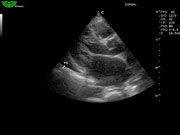

D3P64L 3.0МГц, фазированная решетка.

2.0МГц – 4.4МГц. Применения: кардиология, брюшная полость, акушерство. |